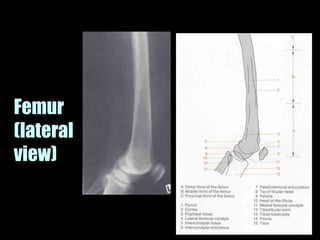

This document provides an overview of normal musculoskeletal imaging. It discusses basic x-ray concepts and densities. It then reviews normal anatomy as seen on x-rays of the skull, spine, pelvis, chest, and extremities. Key anatomical structures are labeled on example x-rays for the shoulder, hip, knee, and foot. Quizzes are included to test recognition of anatomical structures and patient age based on x-rays.